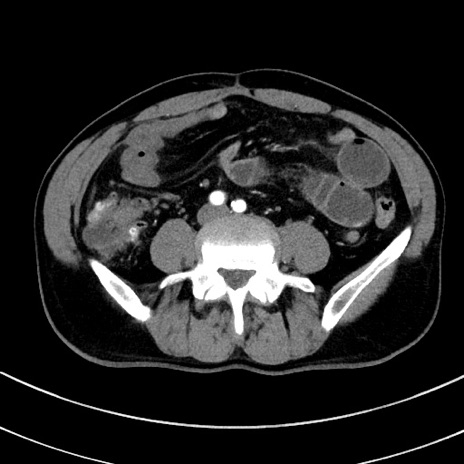

症例8(横断像)

【症例】 60歳代男性

【主訴】 黒色吐物

【現病歴】 4日前から嘔気自覚、2日前の朝食後にも嘔気あり、自分で手で嘔吐反射起こし嘔吐したところ血が混ざっていたため受診。

【既往歴】 5年前汎発性腹膜炎を伴う急性虫垂炎で手術、高血圧、前立腺肥大症、高脂血症

【身体所見】 腹部正中に手術癩痕あり 腹部平坦・軟圧痛なし膨満感あり

【データ】WBC 8400、CRP 4.54